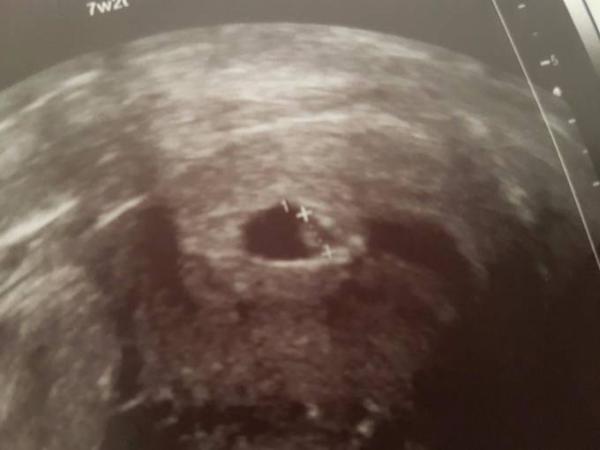

Hallo. Ich war heute beim 1. Termin beim FA. Er konnte 2 Fruchthüllen sehen, aber nur eine embryonale Anlage. Bin von 7+2 SSW auf 6+0 runter gestuft worden. Ich hätte mich wahnsinnig über 2 gefreut, aber mein FA meinte, ich soll mir da keine Hoffnung machen. Habt ihr Erfahrungen in diesem Bereich? Ich bin zwar froh, dass wenigstens ein Herzchen geschlagen hat, aber irgendwie bin ich doch sehr traurig. Mein nächster Termin ist erst in einem Monat. Hab dies auch schon im Zwillingsforum gepostet, da ich sehr verunsichert bin.

In meiner ersten SS hatte ich auch 2 Fruchthöhlen. Bei einer sah man schon eine kleine Anlage, bei der anderen nicht. Auch da sagte mir die Ärztin, sie vermute, dass sich nur eine weiter entwickeln wird. So war es dann auch. Schon beim nächsten Ultraschall war nur noch eine Fruchthöhle zu sehen. Gemerkt habe ich nichts. Die SS lief ganz normal ohne Komplikationen weiter.

Hatte das bei den letzten 2 Schwangerschaften. Bei der vorletzten war die 2. FH schon merklich kleiner als die mit Anlage. Bei dieser SS war die 2. zwar genauso groß, aber leer. Ich war/bin froh, dass sich wenigstens 1 normal entwickelt hatte.